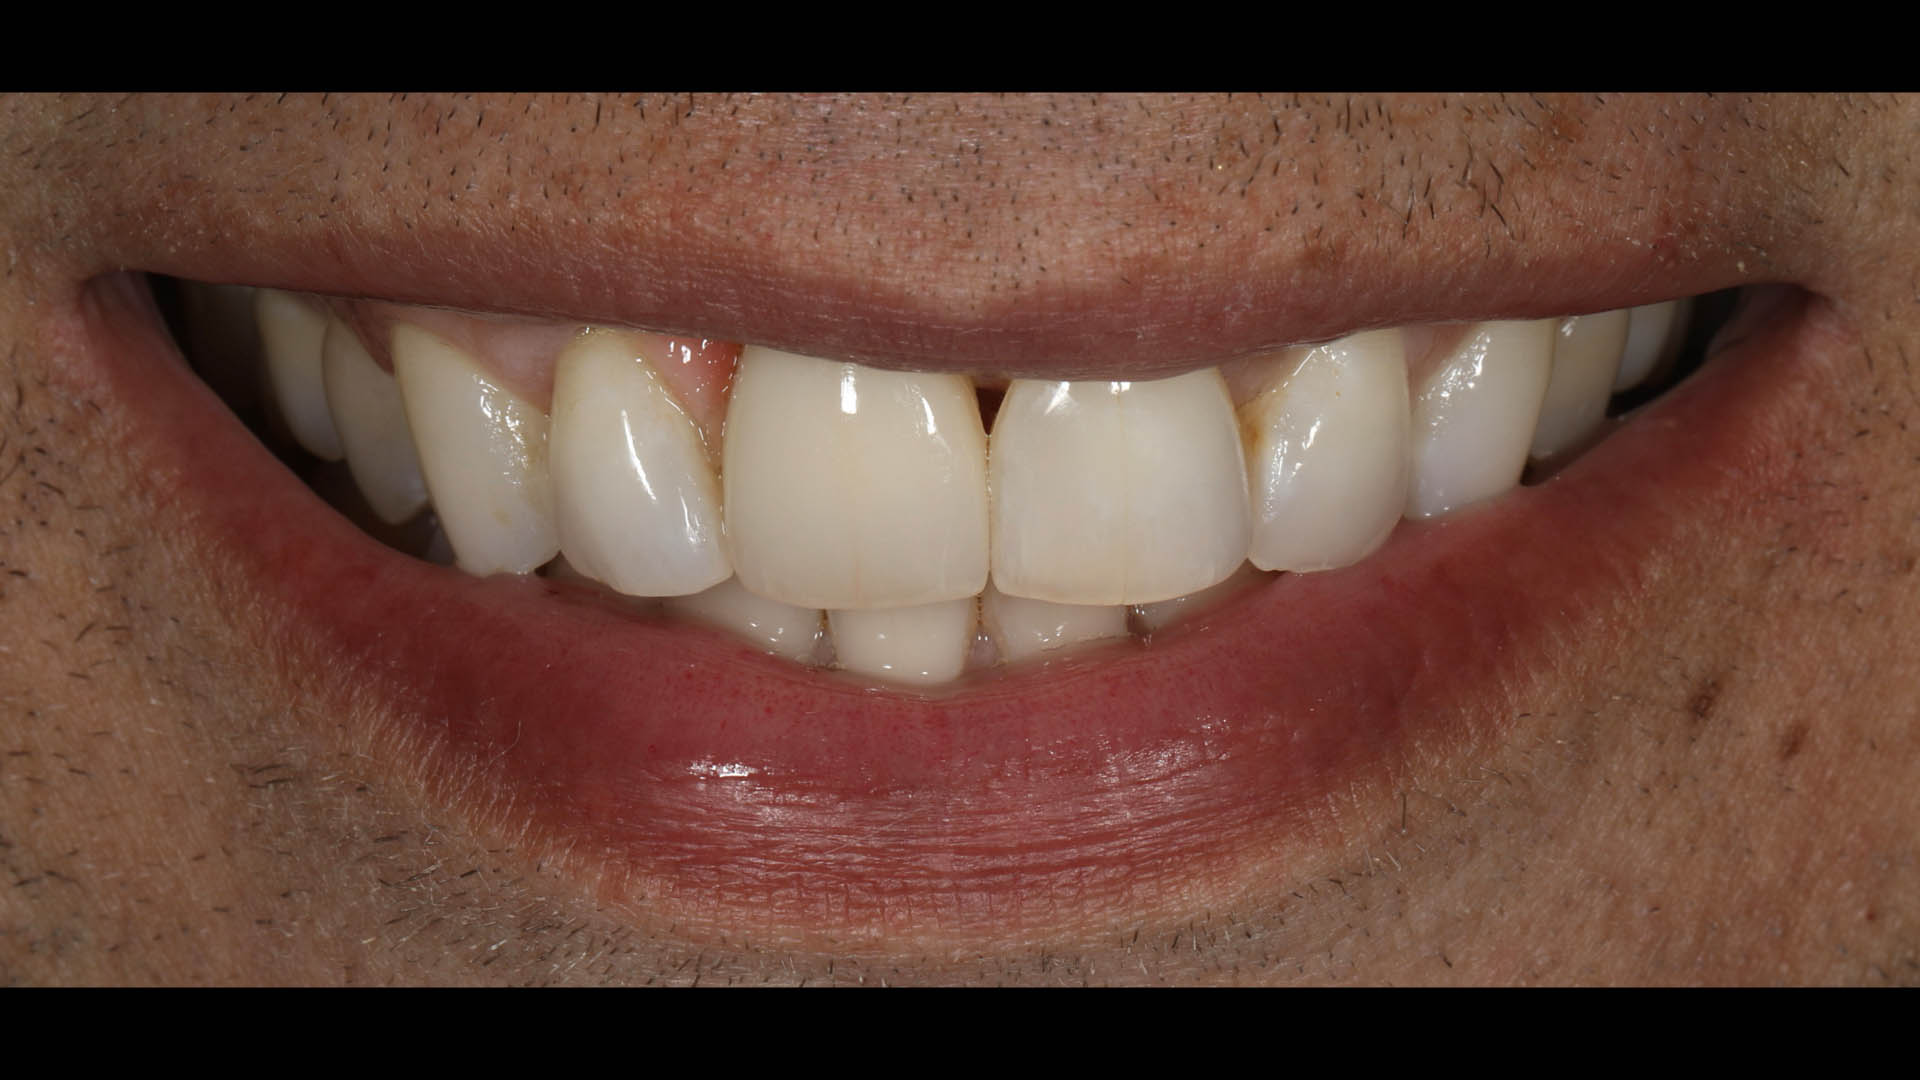

Take a glimpse into the magic of Coral Gables Dentistry through our before and after pictures. See firsthand the incredible smile makeover transformations that have brought confidence and joy to our patients.